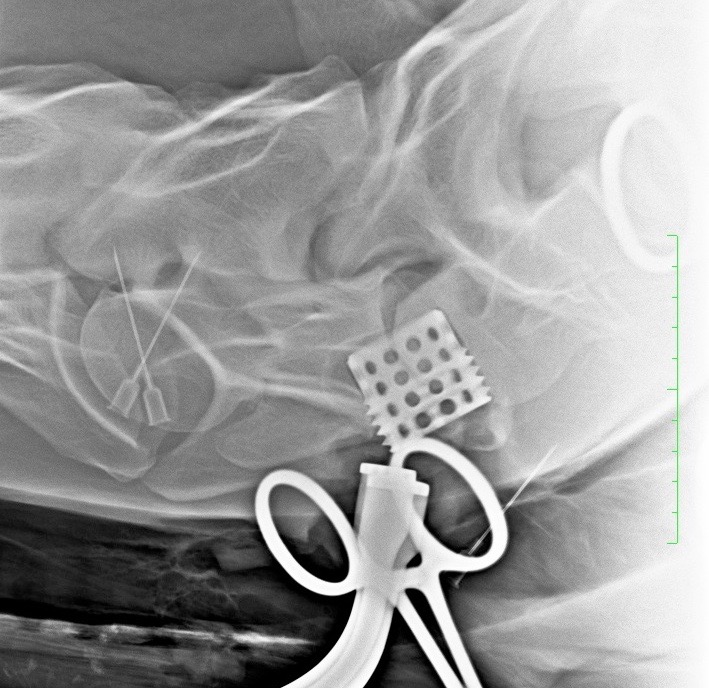

Pokud neurologické vyšetření potvrdí ataxii (stupeň 1–5), je potřeba stanovit její přesnou příčinu. Nejčastěji se jedná o zúžení páteřního kanálu v oblasti krčních obratlů, kde pak dochází k útlaku míchy – Wobblerovu syndromu. Existují ale i další příčiny ataxie, které je potřeba vzít na vědomí, například vrozené abnormality krčních obratlů (vertebrální malformace), úrazy krční páteře, nádory, virové infekce (EHV), bakteriální infekce (abscesy, záněty meziobratlových plotének a kostí) (obr. 2a, b, c), parazitární infekce nebo některé toxiny.

Obrázek 2a, b: Hříbě s ataxií a horečkou způsobenou zánětem kostí obratlů C6–C7. Na CT je jasně patrné výrazné poškození kostí v důsledku infekce (bílé šipky). Na obrázku 2b je stejný případ z jiného pohledu

Obrázek 2c: Postižená kost a meziobratlová ploténka byly chirurgicky odstraněny a oba obratle byly spojeny pomocí ploténky a šroubů